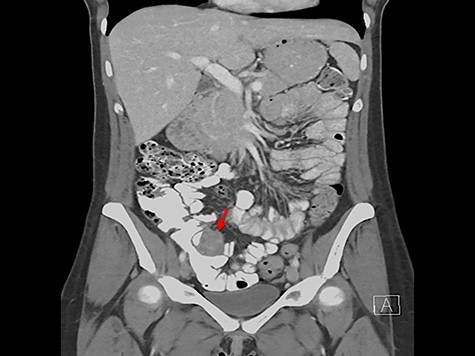

A 33-year-old female presented for surgical evaluation of a possible ileocecal mass and abnormalities found on endoscopy. She presented to an outside hospital 4 months prior to surgical consultation with symptoms of abdominal pain, diarrhea and hematochezia. Computed tomography (CT) imaging demonstratedthickening of the distal descending and proximal sigmoid colon and punctate pneumatosis concerning for ischemic colitis. Endoscopy with mucosal biopsy confirmed the diagnosis of colonic ischemia but also noted marked edema of the cecum and ileocecal valve. Her condition improved with non-surgical supportive care and her hematologic coagulation profile subsequently normalized after stopping oral contraceptive use. Repeat colonoscopy 2 months after hospital discharge confirmed resolution of ischemia but persistent abnormalities of the ileocecal area with cecal fullness and a prolapsed ileocecal valve (Fig. 1), with only lymphoid hyperplasia on biopsy. Repeat CT imaging was obtained and showed a

3.4 × 3.7 cm mass near the ileocecal valve (Fig. 2). Unable to rule out malignancy, surgical resection was recommended for tissue evaluation and the patient underwent laparoscopic right hemicolectomy.